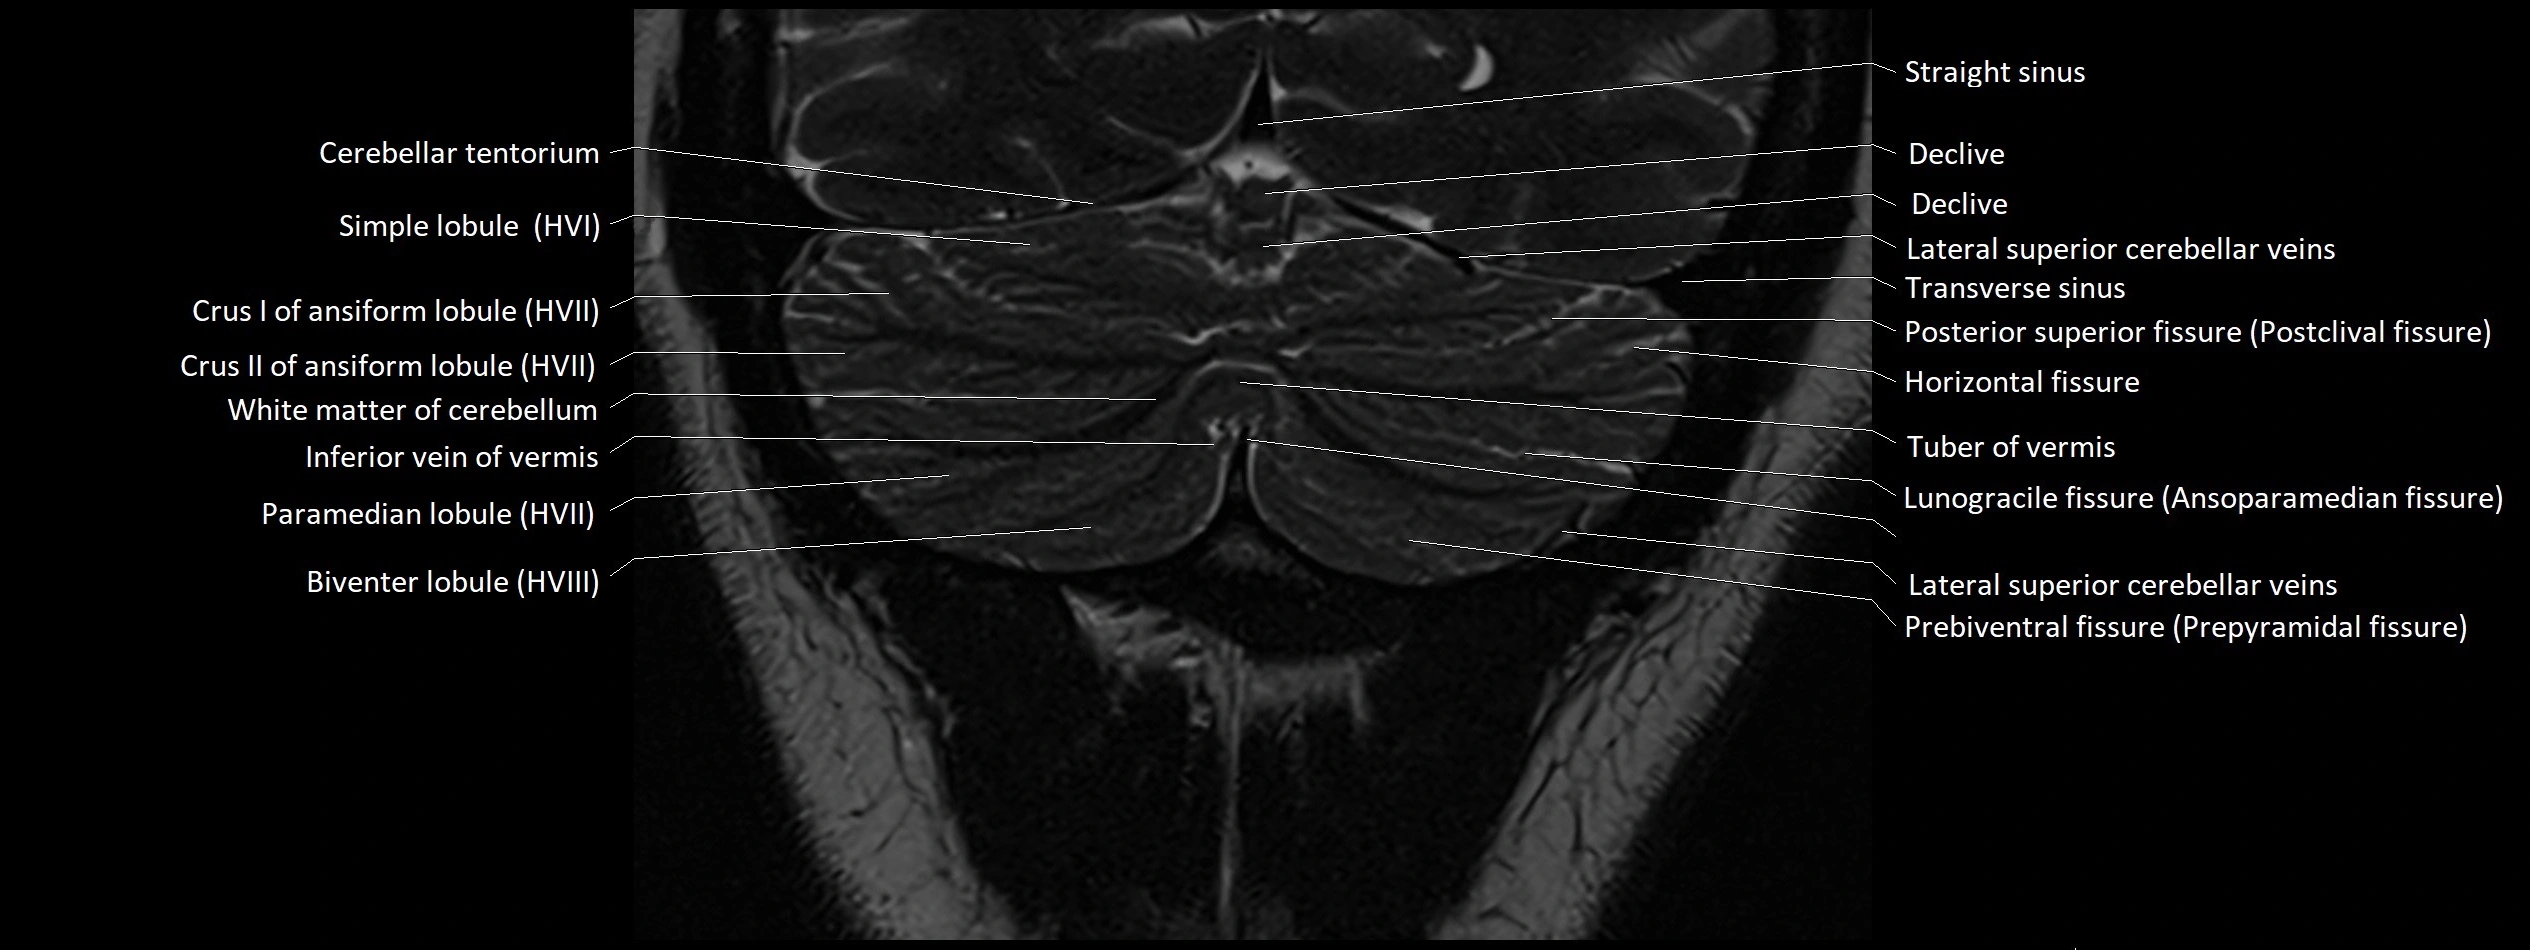

- Cerebellar tentorium

- Declive

- Horizontal fissure (cerebellum)

- Simple lobule

- Simple lobule (HVI) of cerebellum

- Crus I of ansiform lobule of cerebellum

- Crus II of ansiform lobule of cerebellum

- Paramedian lobule

- Paramedian lobule (HVII) of cerebellum

- Biventral lobule (HVIII) of cerebellum

- Straight sinus

- Transverse sinus

- Posterior superior fissure

- Tuber of vermis

- Lunogracle fissure

- Lunogranicile fissure of cerebellum

- Prebiventral fissure

- Inferior vein of vermis